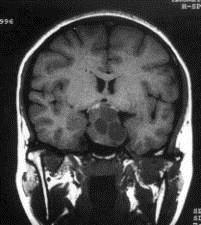

病历摘要:??患者男性,35岁。性功能减退2年,视力下降6月。既往体健。体检:神清,皮肤细腻,毛发稀疏。视力左眼0.3,右眼0.5,双瞳等大等圆,直径3....

问题 病历摘要:??患者男性,35岁。性功能减退2年,视力下降6月。既往体健。体检:神清,皮肤细腻,毛发稀疏。视力左眼0.3,右眼0.5,双瞳等大等圆,直径3.5mm,对光反射稍迟钝,双颞侧偏盲,双眼底视神经乳头原发性萎缩,余神经系统未见异常。 术前的准备应包括下列哪些?提示:拟经蝶窦入路手术治疗